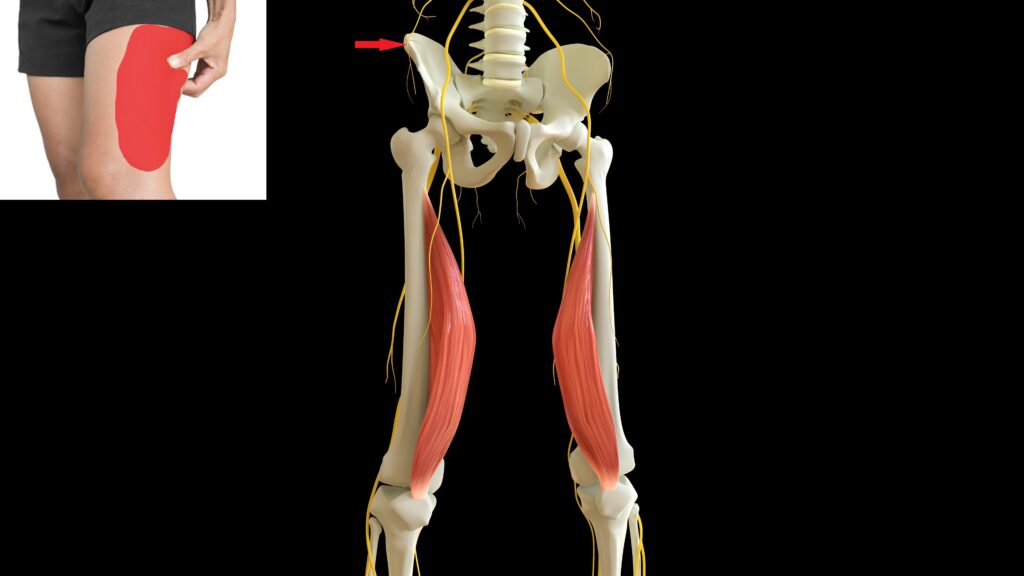

Meralgia Paresthetica ger symtom som stickande, brinnande, eller domnande känsla över en del av ditt utsida lår.

Meralgia Paresthetica beror på att nerven; nervus cutaneus femoralis lateralis kläms in. Ligamentet som sträcker sig från utsidan av höften mot insidan av ditt höftben klämmer ibland in nerven. Ligamentet heter ligament inguinalis.